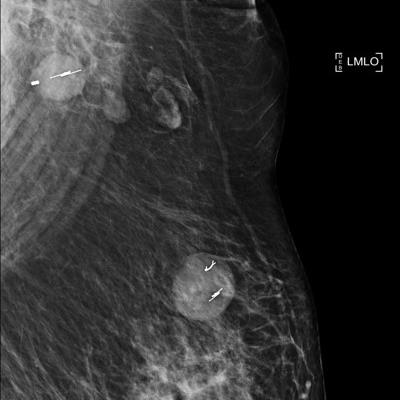

In the review, the ACR found "serious deficiencies" in Radiology Disc's performance, and the facility was asked to provide additional cases. Radiology Disc failed the expanded AMR, however, with 21 of 30 cases not meeting the ACR's standard for clinical image quality. That prompted the ACR to revoke the center's accreditation and the FDA to issue its "serious risk" notification.